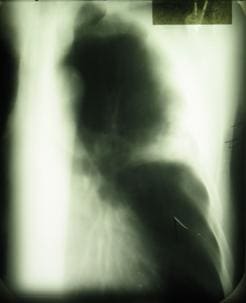

Ателектаз левого легкого, вызванный центральным раком

Сегментарный ателектаз верхней доли левого легкого, вызванный опухолью сегментарных бронхов